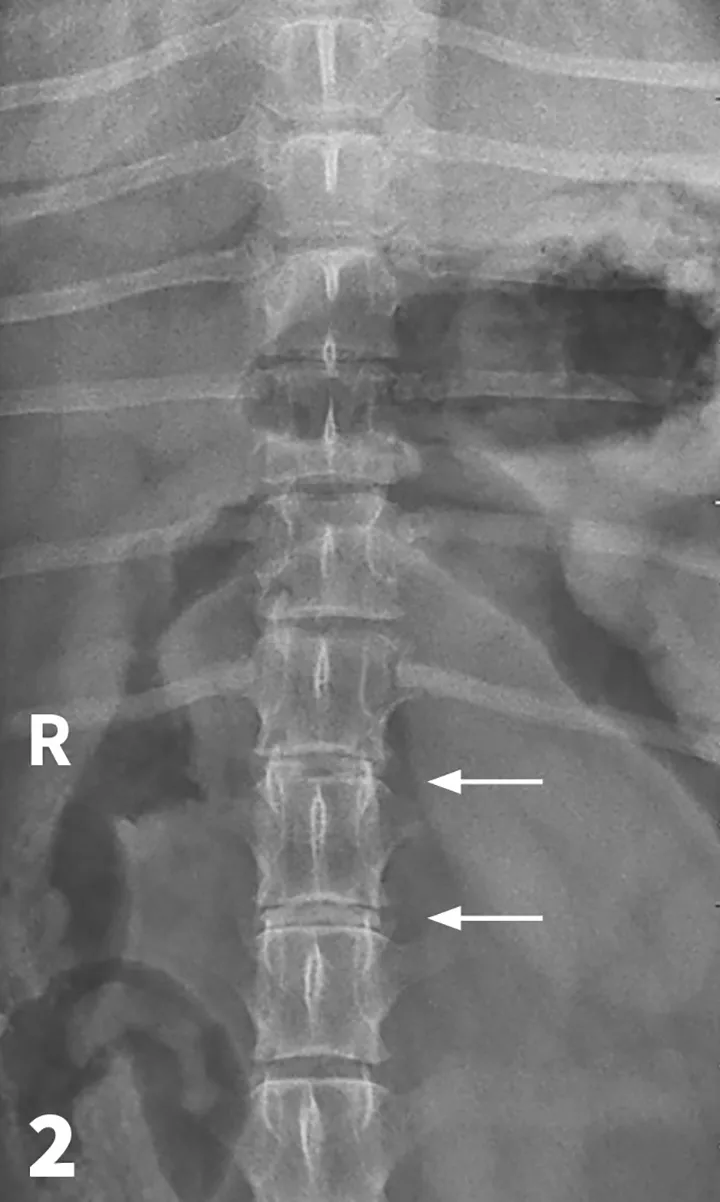

Figure 1

Lateral spinal radiograph. Mineralization and narrowing of the T13-L1 and L1-L2 disc spaces was noted (arrows).

The veterinarian administered 0.02 mg/kg acepromazine IM and 1 mg/kg morphine IM1 and obtained lateral and VD views of the TL vertebral column. (See Figures 1 & 2.) The radiographs showed no evidence of lytic change but did show mineralization and narrowing of the T13-L1 and L1-2 intervertebral disc spaces (arrows).